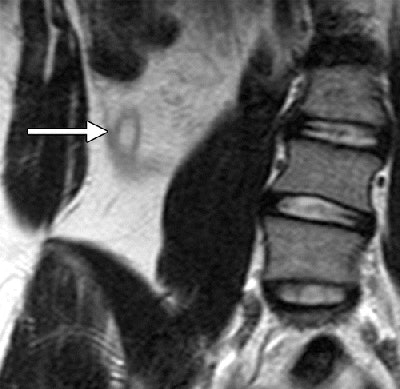

MR image of a 13-year-old girl with acute appendicitis and one day of intermittent abdominal pain. Coronal fast spin-echo T2-weighted MRI of the right lower quadrant shows a dilated, fluid-filled appendix (arrow) with decreased signal intensity in the surrounding fat, indicating inflammation and thickening of the lateral conal fascia. Image courtesy of Radiology.Of the 51 patients who did not undergo an appendectomy, six were lost to follow-up. Clinical follow-up determined that the remaining 45 patients were negative for appendicitis.